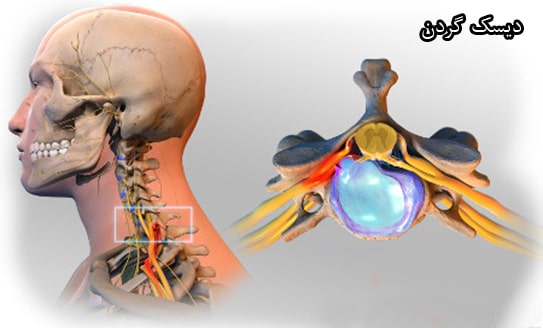

پارگی یا بیرونزدگی دیسک (فتق دیسک) یکی از دلایل اصلی احساس درد در ناحیه گردن و دستها است. دیسکها در حقیقت صفحههای جذب کننده ضربه بین مهرهها بوده و مهرهها از یک مجموعه استخوانهای کوچک که در کنار هم ستون فقرات را ایجاد میکنند، تشکیل شدهاند. بخشی از ستون فقرات در ناحیه گردن امتداد یافته است. در این بخش، دیسکها و مفاصل امکان حرکت آزادانه گردن و ایجاد ثبات برای سر را بر روی بدن فراهم میکنند. علاوه بر این دیسکها نقش بالش را برای محافظت از مهرههای ستون فقرات بر عهده دارند.

با بالا رفتن سن، سطح آب موجود در دیسکها کاهش پیدا میکند. به این ترتیب دیسکها در بدن کوچکتر شده، انعطافپذیری خود را از دست داده، و کارایی آنها به عنوان بالش بین مهرهها کاهش پیدا میکند. هنگامی که یک دیسک از بین برود، بخش خارجی آن دچار پارگی میشود. علت بیرون زدگی دیسک گردن اینست که لایه خارجی دیسک پاره شده و محتویات داخل آن (هسته داخلی) از محل خود خارج گردد.

در صورتی که محتویات داخل دیسک در کانال نخاعی پخش شوند، این شرایط میتواند باعث وارد شدن فشار به اعصاب نخاعی شود. همچنین در هنگام تماس این محتویات با اعصاب، امکان مشاهده یک واکنش شیمیایی به آن وجود دارد. به این ترتیب اعصاب کانال نخاعی ملتهب شده، ورم کرده و در نتیجه این شرایط بیمار با درد مواجه میشود. علاوه بر این، پارگی و بیرونزدگی دیسک میتواند باعث وارد شدن فشار به کانال نخاعی شود.